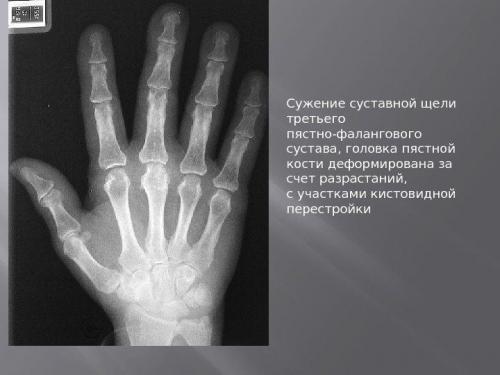

При этом воспаление и болевой синдром при начальной степени артроза отсутствуют. Если в этот период сделать рентгеновский снимок, то на нем можно заметить сужение межсуставной щели, особенно если это касается кистей рук, коленей. Человек начинает ощущать незначительный дискомфорт, которое он воспринимает как обычное переутомление. Иногда можно слышать редкие щелчки, когда пораженный сустав приходит в действие. Совсем легкие боли могут появляться после повышенной нагрузки.

- I стадия. Начало болезни суставов выдает себя характерным хрустом или щелчком при сгибании/разгибании пальцев. Периодически возникающий болевой дискомфорт проявляется после активной физической работы или в момент магнитных бурь. Суставы начинают ныть, отдают тупой пронизывающей или распирающей болью. Острые приступы на начальной фазе заболевания нетипичны. Однако даже при этой степени клинической патологии можно наблюдать периодически возникающую отечность в межфаланговом сочленении;

- II стадия клинического развития болезненного состояния – это интенсивное нарастание болевого рефлекса, при котором ощущается жгучая пульсирующая. Частое беспокойство она доставляет человеку в ночное время. Там, где ранее наблюдалась припухлость, образуются костные наросты, илис симметричным расположением на обеих руках. В это же время отмечается заметная деформация в суставах пальцев рук, которая ограничивает подвижность;